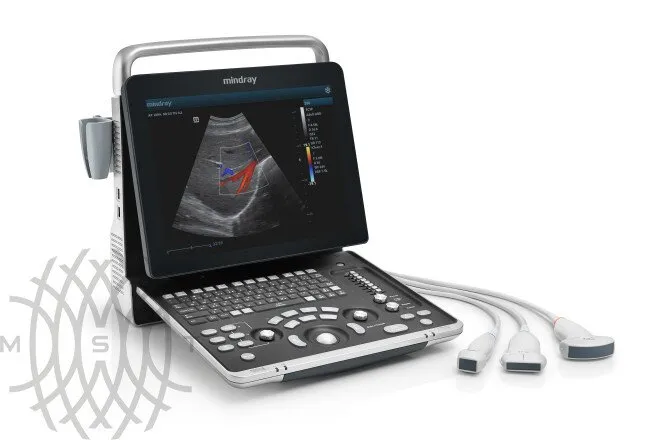

УЗИ аппарат Mindray Z60 портативный

Аппарат УЗИ Mindray Z60 является новой, переосмысленной версией популярного сканера Mindray DP-50. Аппарат оснащен двумя портами для подключения датчиков и опционально может иметь дополнительный третий порт. Система поддерживает такие продвинутые технологии как компрессионная эластография, а так же 3D/4D исследование и может быть укомплектован более современными датчиками.

Основные преимущества новой системы заключаются в компактном дизайне, возможности регулировки угла наклона монитора до 60 градусов, 15” экран с антибликовым покрытием, жесткий диск 1Т, батарея на 1,5 часа автономной работы, до 3-х встроенных портов для датчиков.